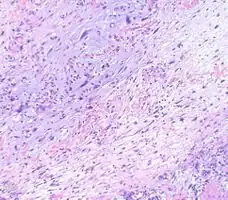

- Myxofibrosarcoma-pathology